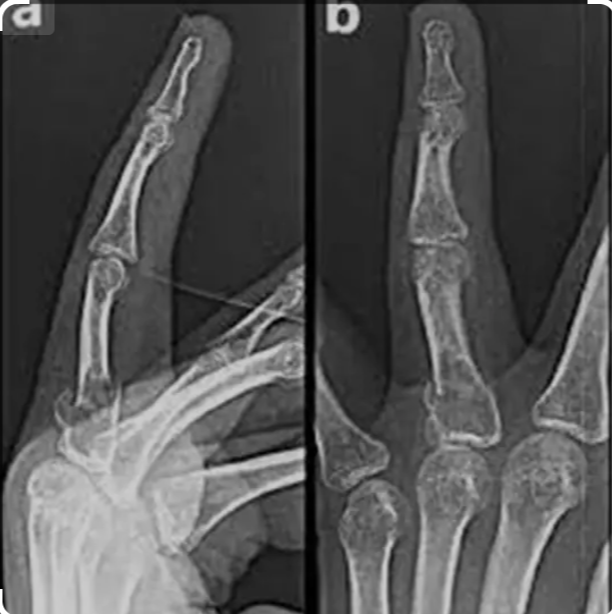

Medifyhome provides X-ray Left Finger AP & LAT at affordable prices. An X-ray of the left finger using anteroposterior (AP) and lateral (LAT) views is a diagnostic imaging procedure commonly utilized to evaluate fractures, dislocations, deformities, infections, or other abnormalities affecting the finger. The AP view provides a frontal perspective of the finger, allowing for assessment of bone alignment, joint spaces, and overall bony architecture, while the lateral view offers a side profile, which is crucial for visualizing the alignment of the phalanges and detecting subtle fractures or dislocations that may not be apparent in the AP view. These views are particularly useful in diagnosing conditions such as fractures, arthritis, osteomyelitis, or soft tissue injuries. If you are looking for an X-ray Left Finger AP & LAT, Medifyhome collaborates with NABL and NABH-certified diagnostic imaging centers to provide cost-effective yet high-quality X-ray tests. Book an X-ray with Medifyhome today by visiting our website or calling +919100907036 / +919100907622 for affordable and hassle-free medical services.

The anteroposterior (AP) and lateral (LAT) views X-ray of the left finger are radiographic imaging techniques used to assess the bones and joints of the fingers. The AP view provides a front-to-back image, while the lateral view gives a side-on image, allowing clear visualization of bone alignment, fractures, joint spaces, and soft tissue.